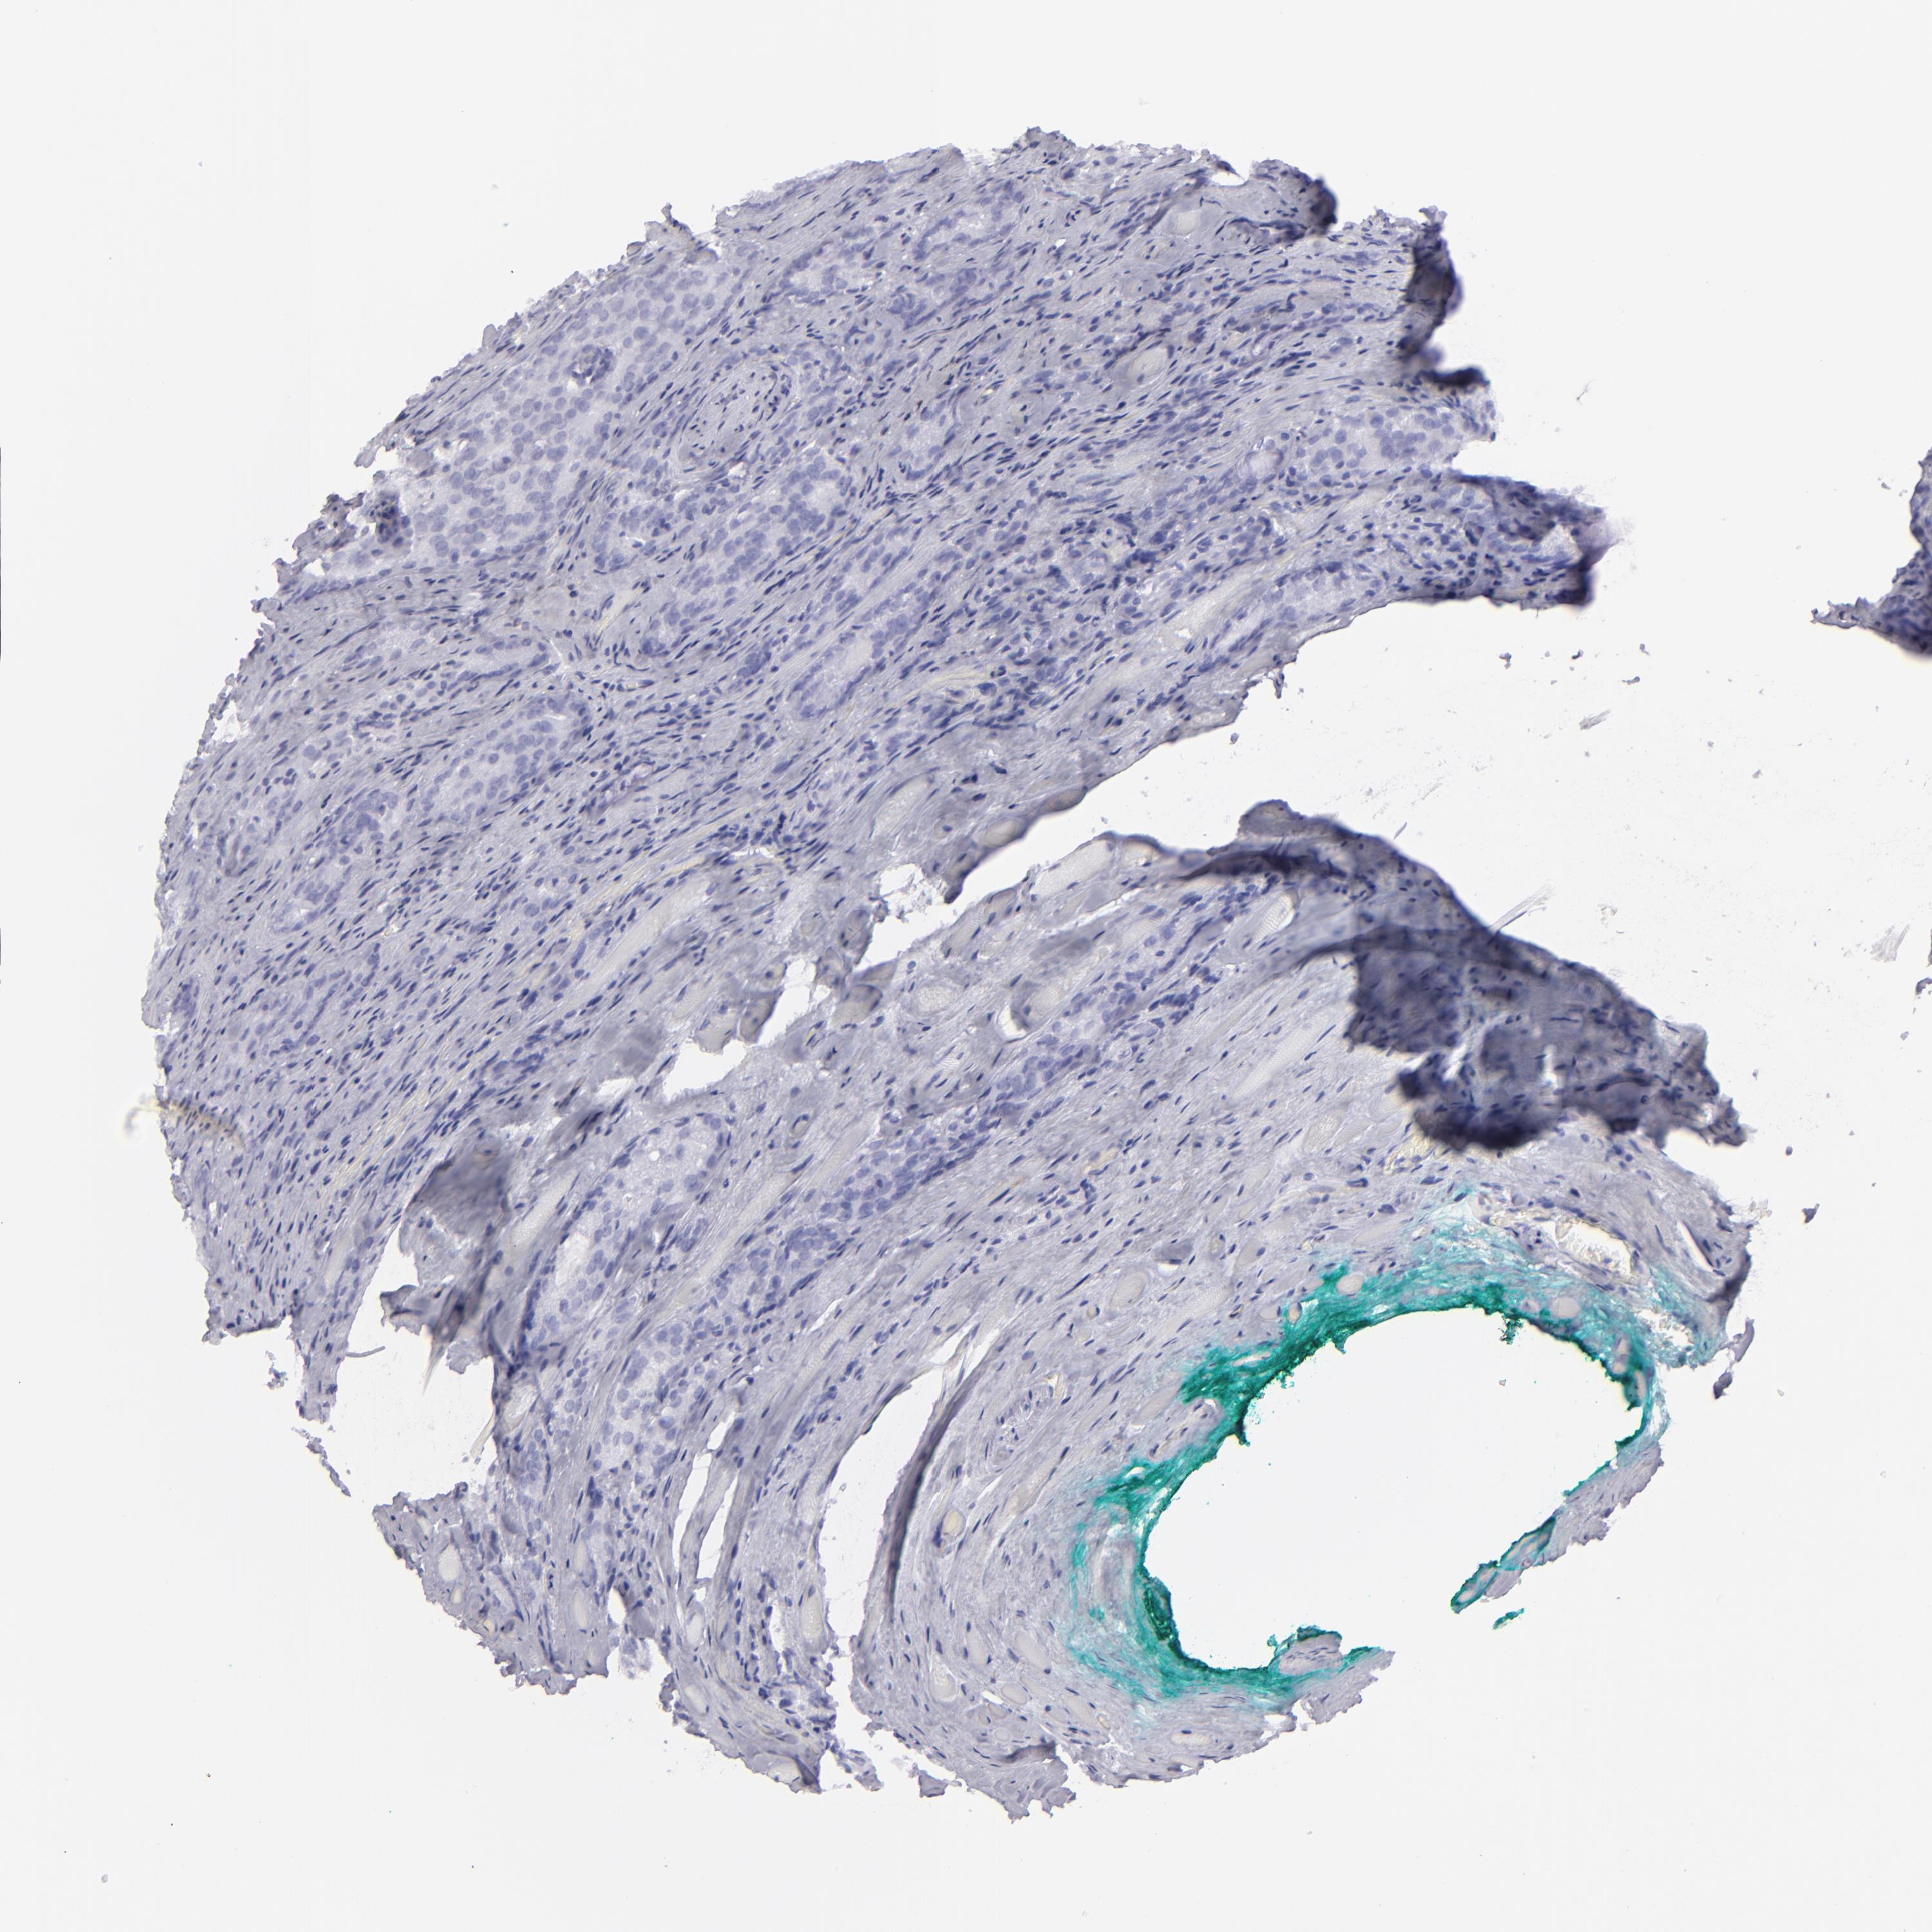

PROSTATE CANCER - Protein expressioni

A mouse-over function shows sample information and annotation data. Click on an image to view it in a full screen mode. Samples can be filtered based on level of antibody staining by selecting one or several of the following categories: high, medium, low and not detected. The assay and annotation is described here.

Note that samples used for immunohistochemistry by the Human Protein Atlas do not correspond to samples in the TCGA dataset.

Antibody stainingi

Antibody staining in the annotated cell types in the current human tissue is reported as not detected, low, medium, or high, based on conventional immunohistochemistry profiling in selected tissues. This score is based on the combination of the staining intensity and fraction of stained cells.

Each image is clickable and will lead to virtual microscopy that enables deeper exploration of all samples and also displays staining intensity scores, fraction scores and subcellular localization as well as patient and tissue information for each sample.

Antibody HPA030188

Antibody HPA030189

Antibody CAB002210

Staining

Adenocarcinoma, High grade

Adenocarcinoma, Low grade

Adenocarcinoma, Medium grade